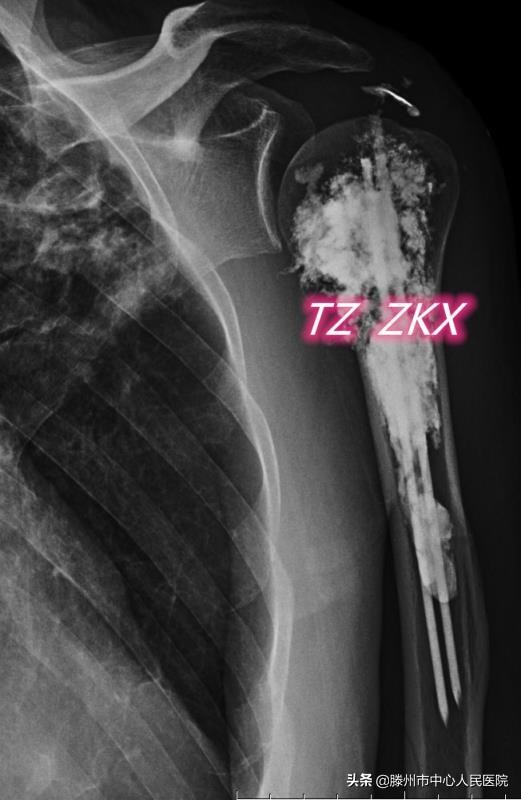

8月11日,張開賢主任醫(yī)師團(tuán)隊(duì)在麻醉科的協(xié)助下,采用臂叢麻醉,在CT引導(dǎo)下經(jīng)皮穿刺,首先對(duì)病變區(qū)域進(jìn)行微波消融,利用高溫使腫瘤發(fā)生凝固性壞死,然后在肱骨髓腔內(nèi)置入兩根克氏針,最后注射骨水泥,使克氏針、骨水泥與肱骨融合在一起,從而起到殺滅腫瘤、緩解疼痛、增加骨骼的穩(wěn)定性、預(yù)防病理性骨折的作用。